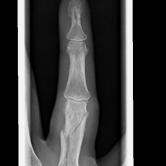

Röntgenbilder